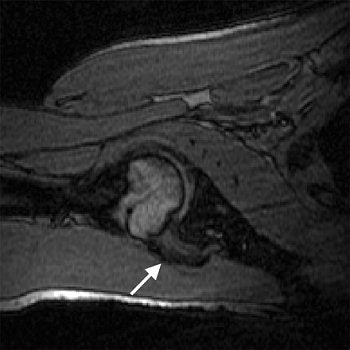

| Transverse 3D gradient-echo MR images (30/10) with volunteer in neutral position (above), unloaded ABER position at 90° external rotation (middle), and 111° external rotation (below). Note infraspinatus tendon (arrow) deformed between the greater tuberosity and posterosuperior glenoid in the loaded study. |

Based on the image evaluation, contact was observed between the supraspinatus and the posterosuperior glenoid in the unloaded and loaded ABER positions in all eight volunteers. Again, in all eight subjects, contact was noted between the infraspinatus near the insertion and posterior glenoid in the loaded and unloaded positions. Four cases were deemed grade 2. Intraobserver agreement between the two radiologists on supraspinatus and infraspinatus tendon contact with the glenoid was excellent (k = 0.875).

The researchers also assessed minimum distances and noted changes in distance in the loaded ABER position. They found that the minimum distance between the supraspinatus insertion and the acromion dipped from 16.9 mm to 5.7 mm, while the infraspinatus to glenoid distance went from 38.4 mm to 3.6 mm. The supraspinatus to glenoid distance went from 35 mm to 6.6 mm. Finally, the distance between the greater tuberosity and glenoid decreased from 21.5 mm to 3.6 mm.